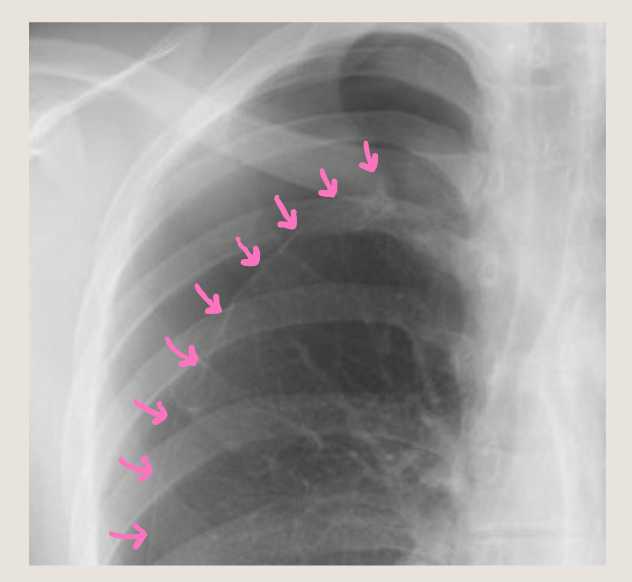

さらに拡大しました。しぼんだ肺のラインが見えます!